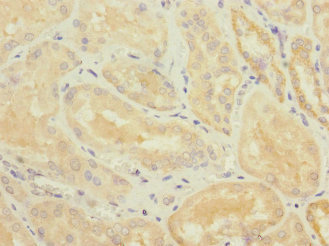

圖片:

應用范圍:ELISA, IHC

Application Recommended Dilution IHC 1:20-1:200 -